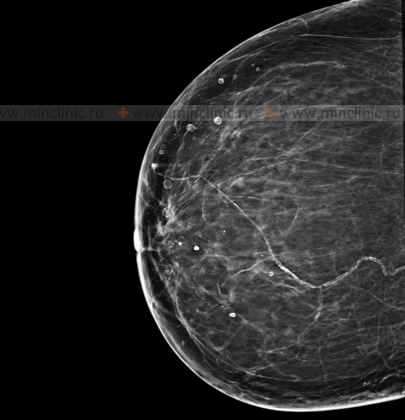

Breast Calcifications

Detection and Significance

Breast calcifications are small, limited accumulations or deposits of calcium salts within the breast tissue. These are a very common finding on mammograms and are usually not palpable (cannot be felt as a lump) in the breast tissue. Mammography is highly effective at detecting and characterizing breast calcifications.

The significance of breast calcifications depends largely on their size, shape, pattern, and distribution:

- Macrocalcifications: These are larger, coarser calcifications (typically >0.5 mm). They are almost always benign and are commonly associated with aging, previous injuries, inflammation, or benign conditions like fibroadenomas or cysts. They usually do not require further investigation beyond routine screening.

- Microcalcifications: These are tiny specks of calcium, often smaller than 0.5 mm. While most microcalcifications are also benign, certain patterns of microcalcifications found during mammography can be suspicious. For example, clusters of pleomorphic (varying in shape and size), linear, or branching microcalcifications may indicate excessive activity of breast tissue cells (e.g., ductal carcinoma in situ - DCIS, an early non-invasive form of breast cancer) and are often considered by a mammologist as an early manifestation of a potentially cancerous process in a woman. Such findings typically warrant further evaluation, such as magnification views on mammography, ultrasound, or biopsy (e.g., stereotactic core biopsy).

It is important to note that the presence of calcifications does not automatically mean cancer, but specific types and patterns require careful assessment by a radiologist specializing in breast imaging.